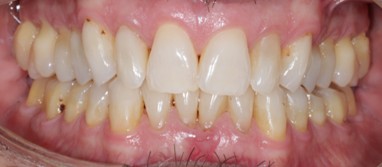

As a dentist specializing in Prosthodontics, Dr. Yepez’ philosophy has always been driven by providing excellent treatment to her patients in a caring and comfortable atmosphere, emphasizing in prevention and education. Her goal is to exceed the expectations of her patients by providing appropriate and quality care allowing them to make an educated decision about their dental treatments.